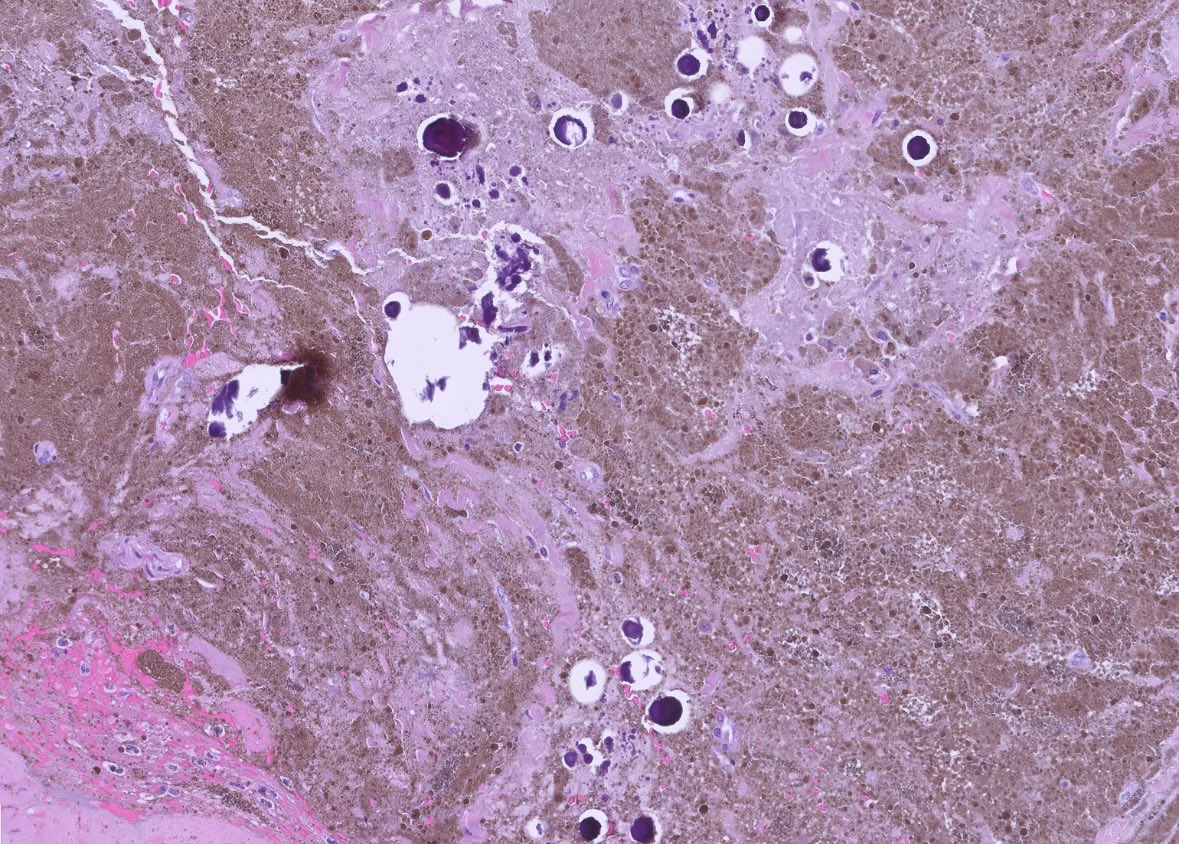

Mass of spine 32M. Malignant Melanotic Nerve Sheath Tumor (MMNST). Heavily pigmented tumor. Note the frequent psammoma bodies here, a clue to the correct diagnosis. Syndrome/molecular? Other features of this syndrome? #pathx #pathtwitter #neuropath #neuropathology #cnspathology

0

5

31